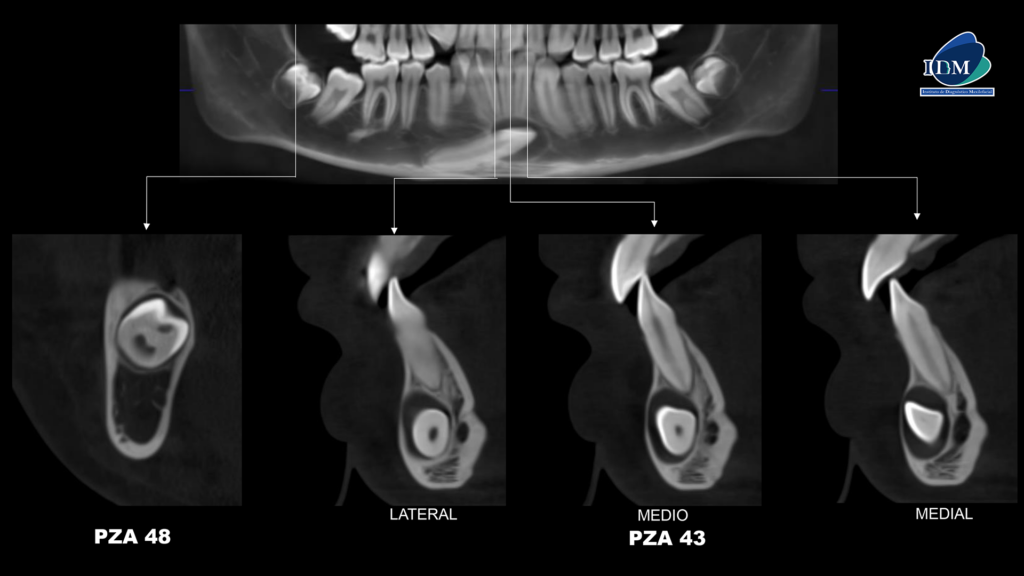

En la radiografía panorámica (Figura 1), se observa pieza 83 en persistencia; pieza 43 retenida, mesioangulada y proyectada en sínfisis mandibular, además se observó una imagen radiolúcida pericoronaria redondeada, de limites definidos y bordes corticalizados. Así mismo la pieza 48 se encontraba en evolución intraósea con presencia de imagen radiolúcida definida ubicada por debajo del limite amelodentinario.

A la evaluación de la tomografía volumétrica (cone beam) en los cortes axiales (Figura 2) y transaxiales (Figura 3), se observa pieza 43 retenida, mesioangulada, localizada en sínfisis mandibular, orientada hacia la tabla ósea vestibular y con presencia de imagen isodensa pericoronaria de forma ovalada de limites definidos insertada a nivel de la unión amelocementaria, de dimensión de 9.9 x 12.15 x 13.5 mm que se extiende de mesial de 33 a distal de 42 ocasionando una leve expansión y adelgazamiento de la tabla ósea vestibular. A demás de presentar en la pieza 48 la presencia de imagen hipodensa ovalada localizada por debajo del limite amelodentinario y ubicación central.

En las reconstrucciones 3D se representa la lesión quística pericoronaria de la pieza 43 y la imagen intracoronaria de la pieza 48 (Figura 4 y 5).

- Quiste dentígero asociado a pieza 43. Reabsorción intracoronaria preeruptiva en pieza 48.